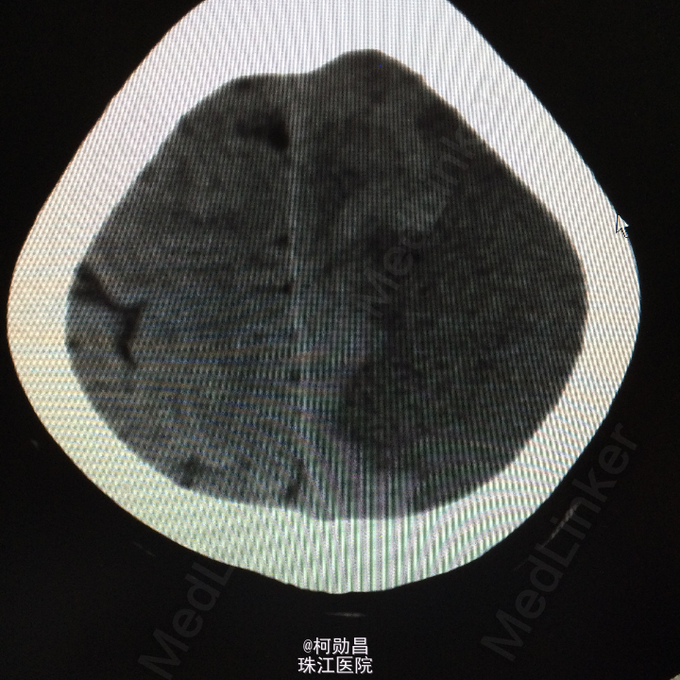

查体:神志呈昏睡状态,言语不能,精神差,双侧瞳孔不等大,左侧3mm,对光反射消失;右侧瞳孔2,mm,对光反射灵敏,右侧肢体肌力0级,左侧肢体肌力5级,右侧肢体肌张力减低,余未见异常。 辅助检查:左侧大脑半球累计岛叶、基底节区(以颞顶叶为主)大片状低密度影,考虑脑梗塞;中线结构明显右移。